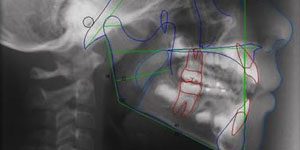

Ortodontia

A ortodontia tem por base a correção da posição dos dentes e maxil...

Serviço de Radiologia Dentária

A clínica encontra-se equipada com os mais avançados equipamentos de...